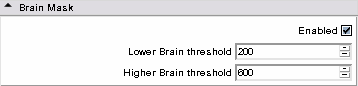

- Brain Mask panel: